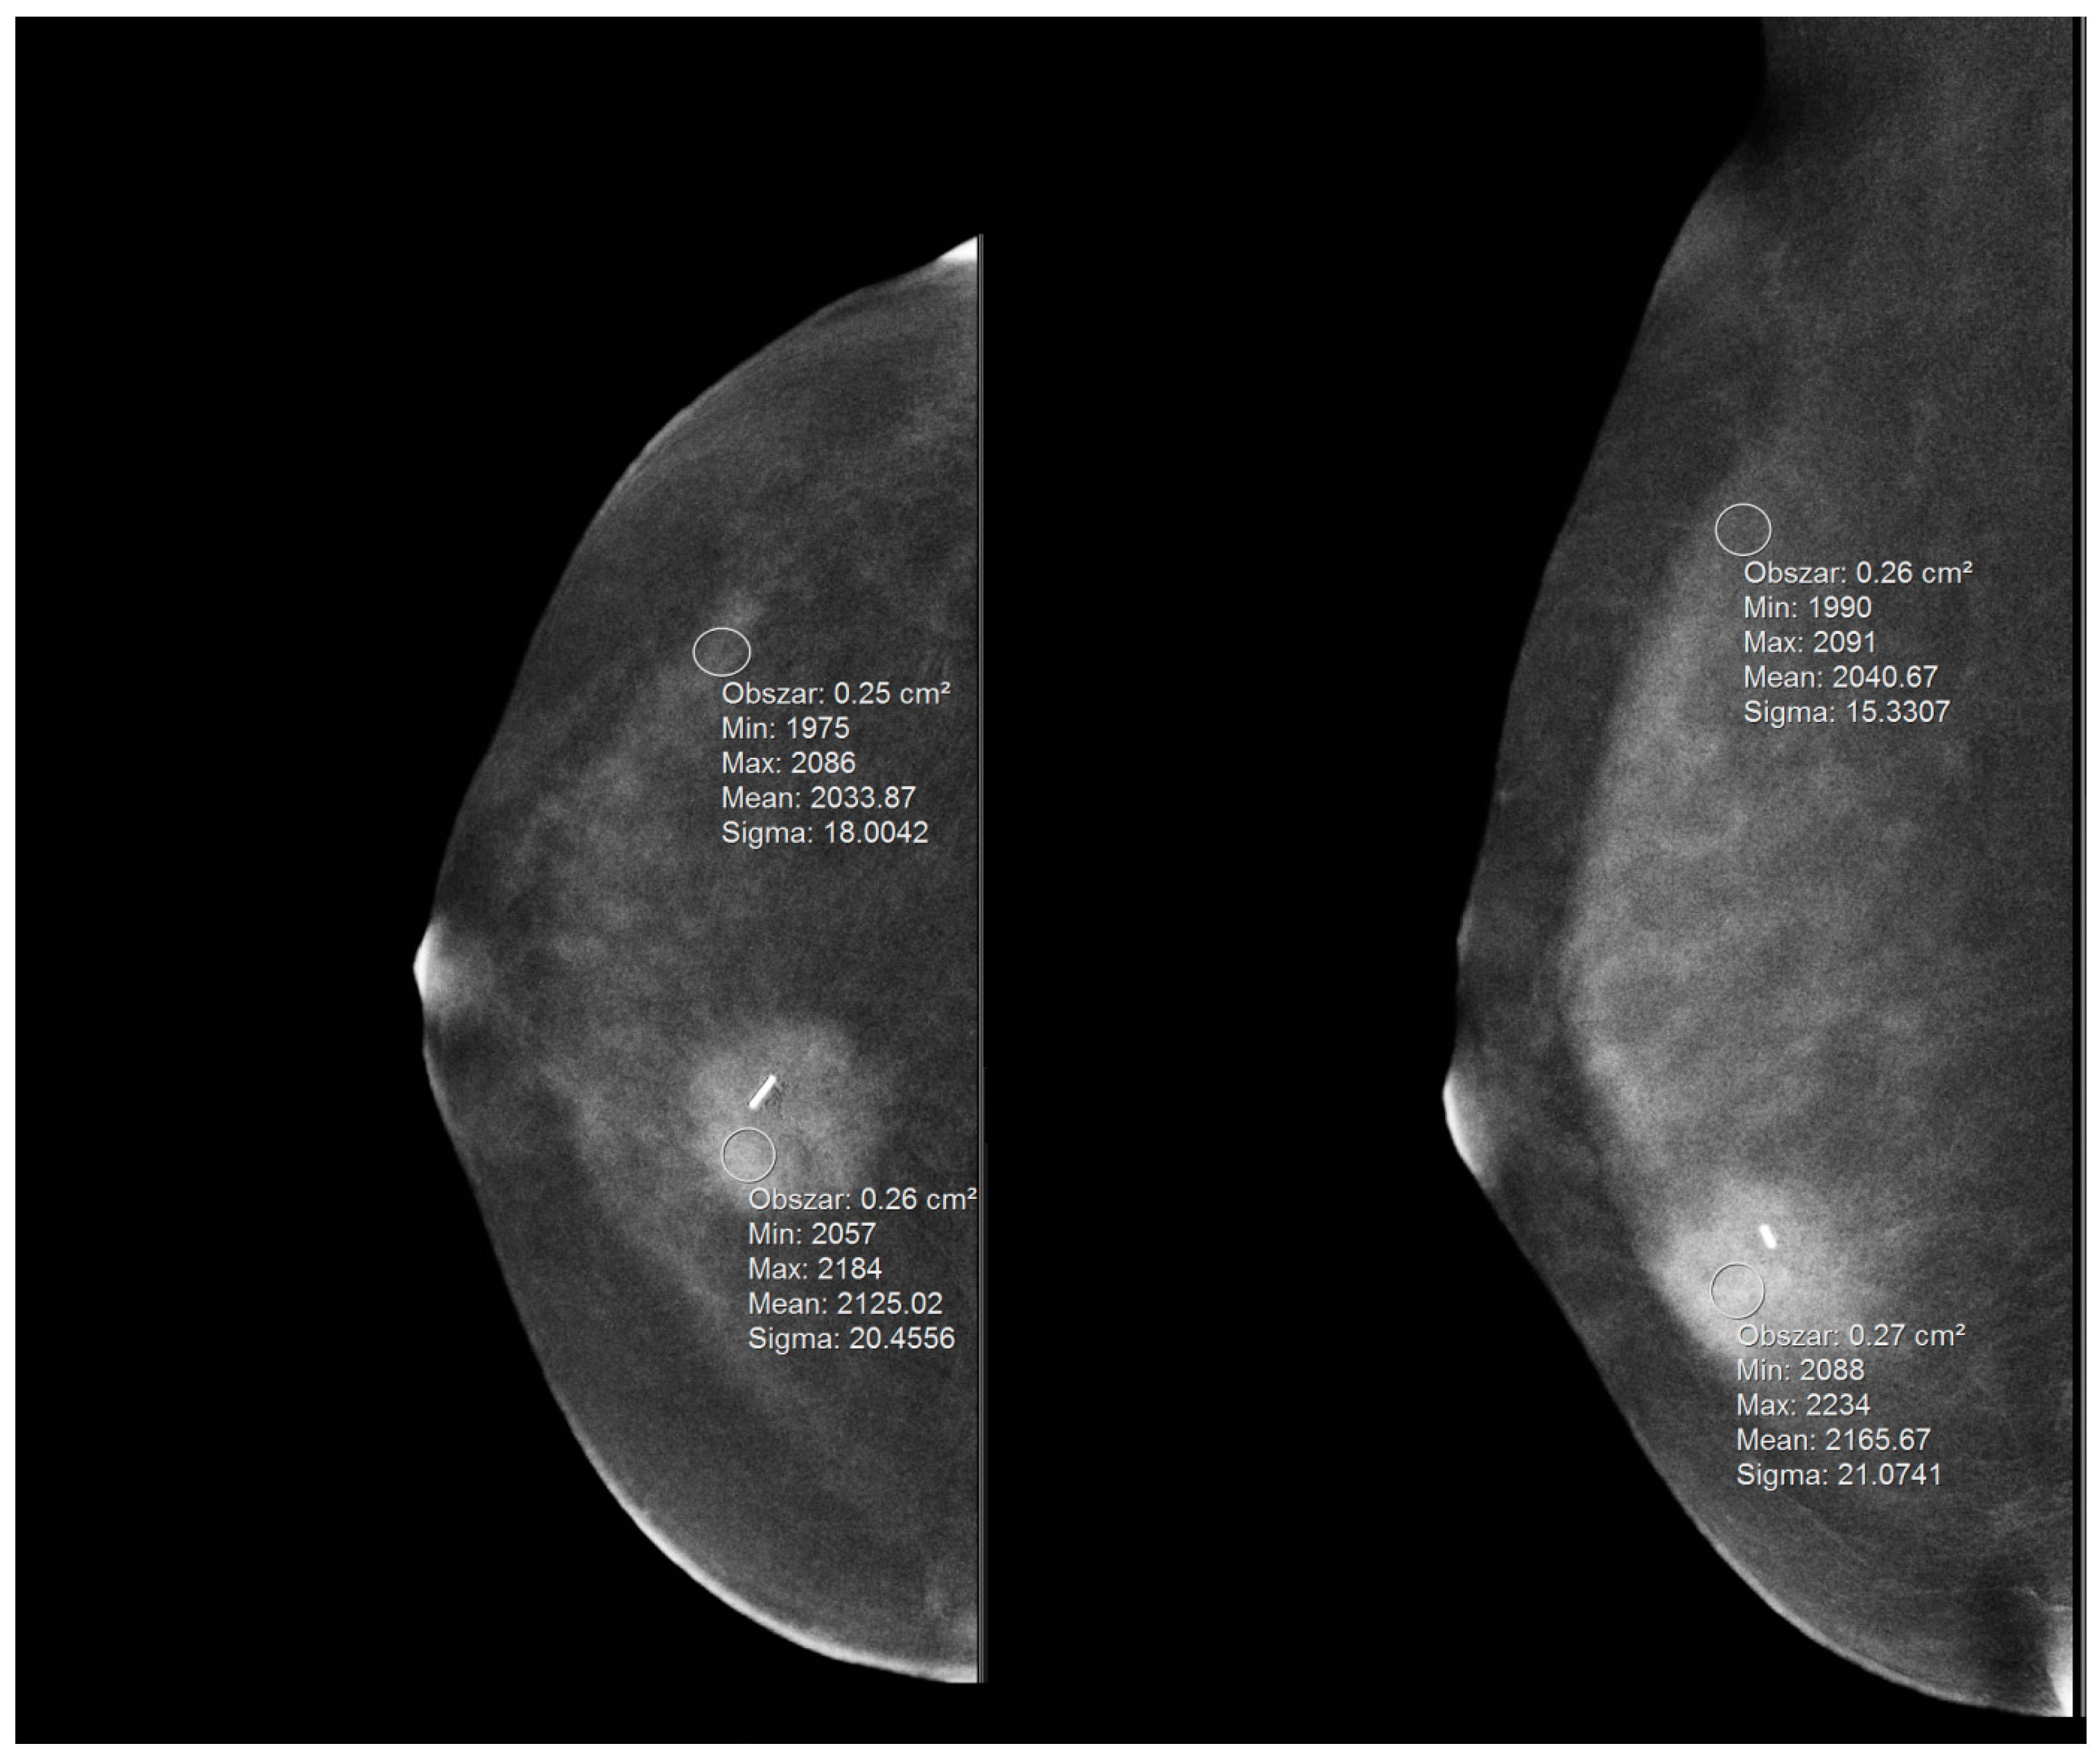

- ls—signal in the lesion;

- bs—signal in the background (parenchyma);

- σ—standard deviation of the signal in the parenchyma.